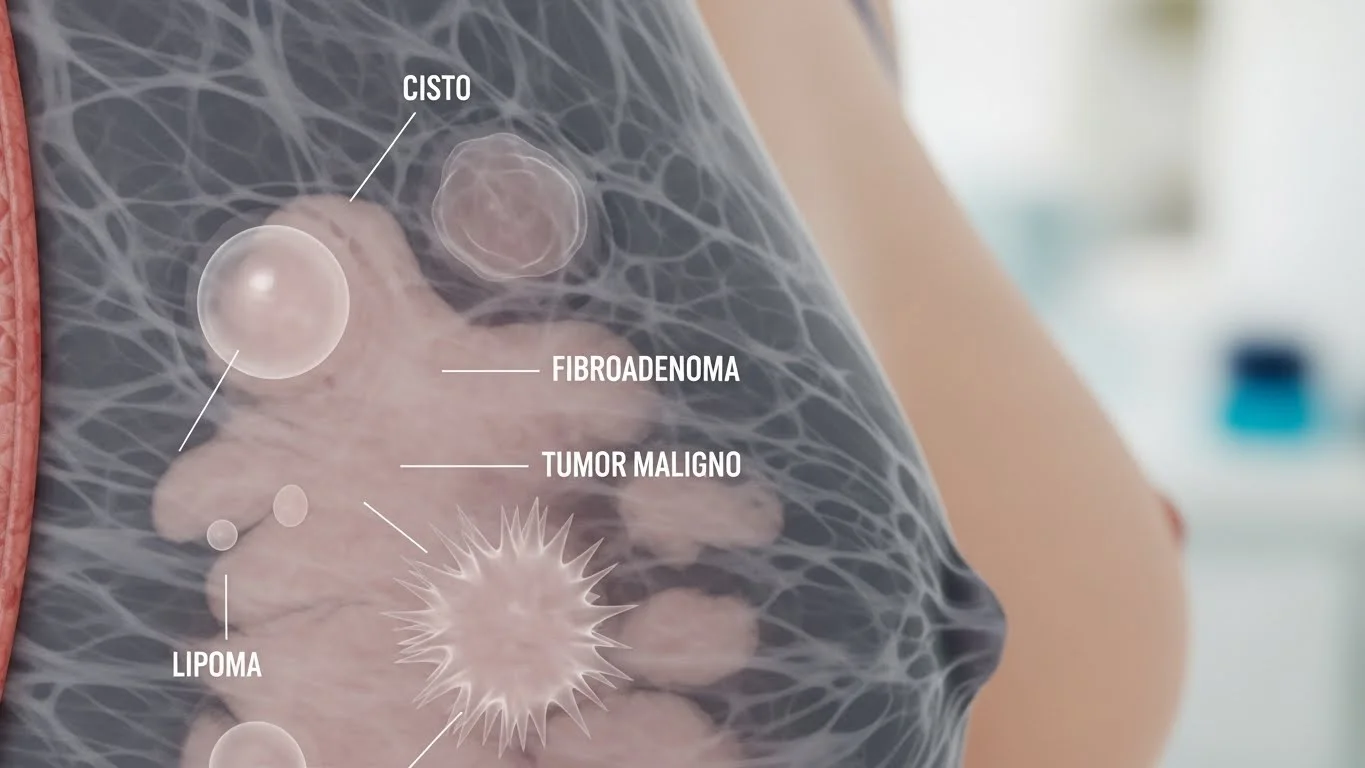

Cistos e Nódulos Mamários: Entenda as Diferenças Cisto de mamaÉ uma bolsinha cheia de líquido, muito comum principalmente a partir...

Tipos de “caroços” na mama: o que podem significar? Descobrir um “caroço” na mama é motivo de preocupação para muitas...